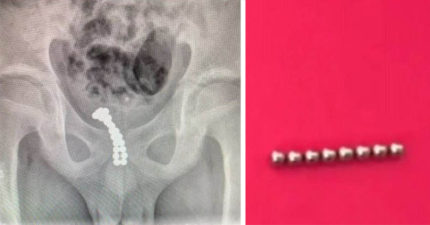

11歲男童把26顆磁球「塞進GG」結果尿血腫痛,醫生嚇壞只好「把磁球推進膀胱」!